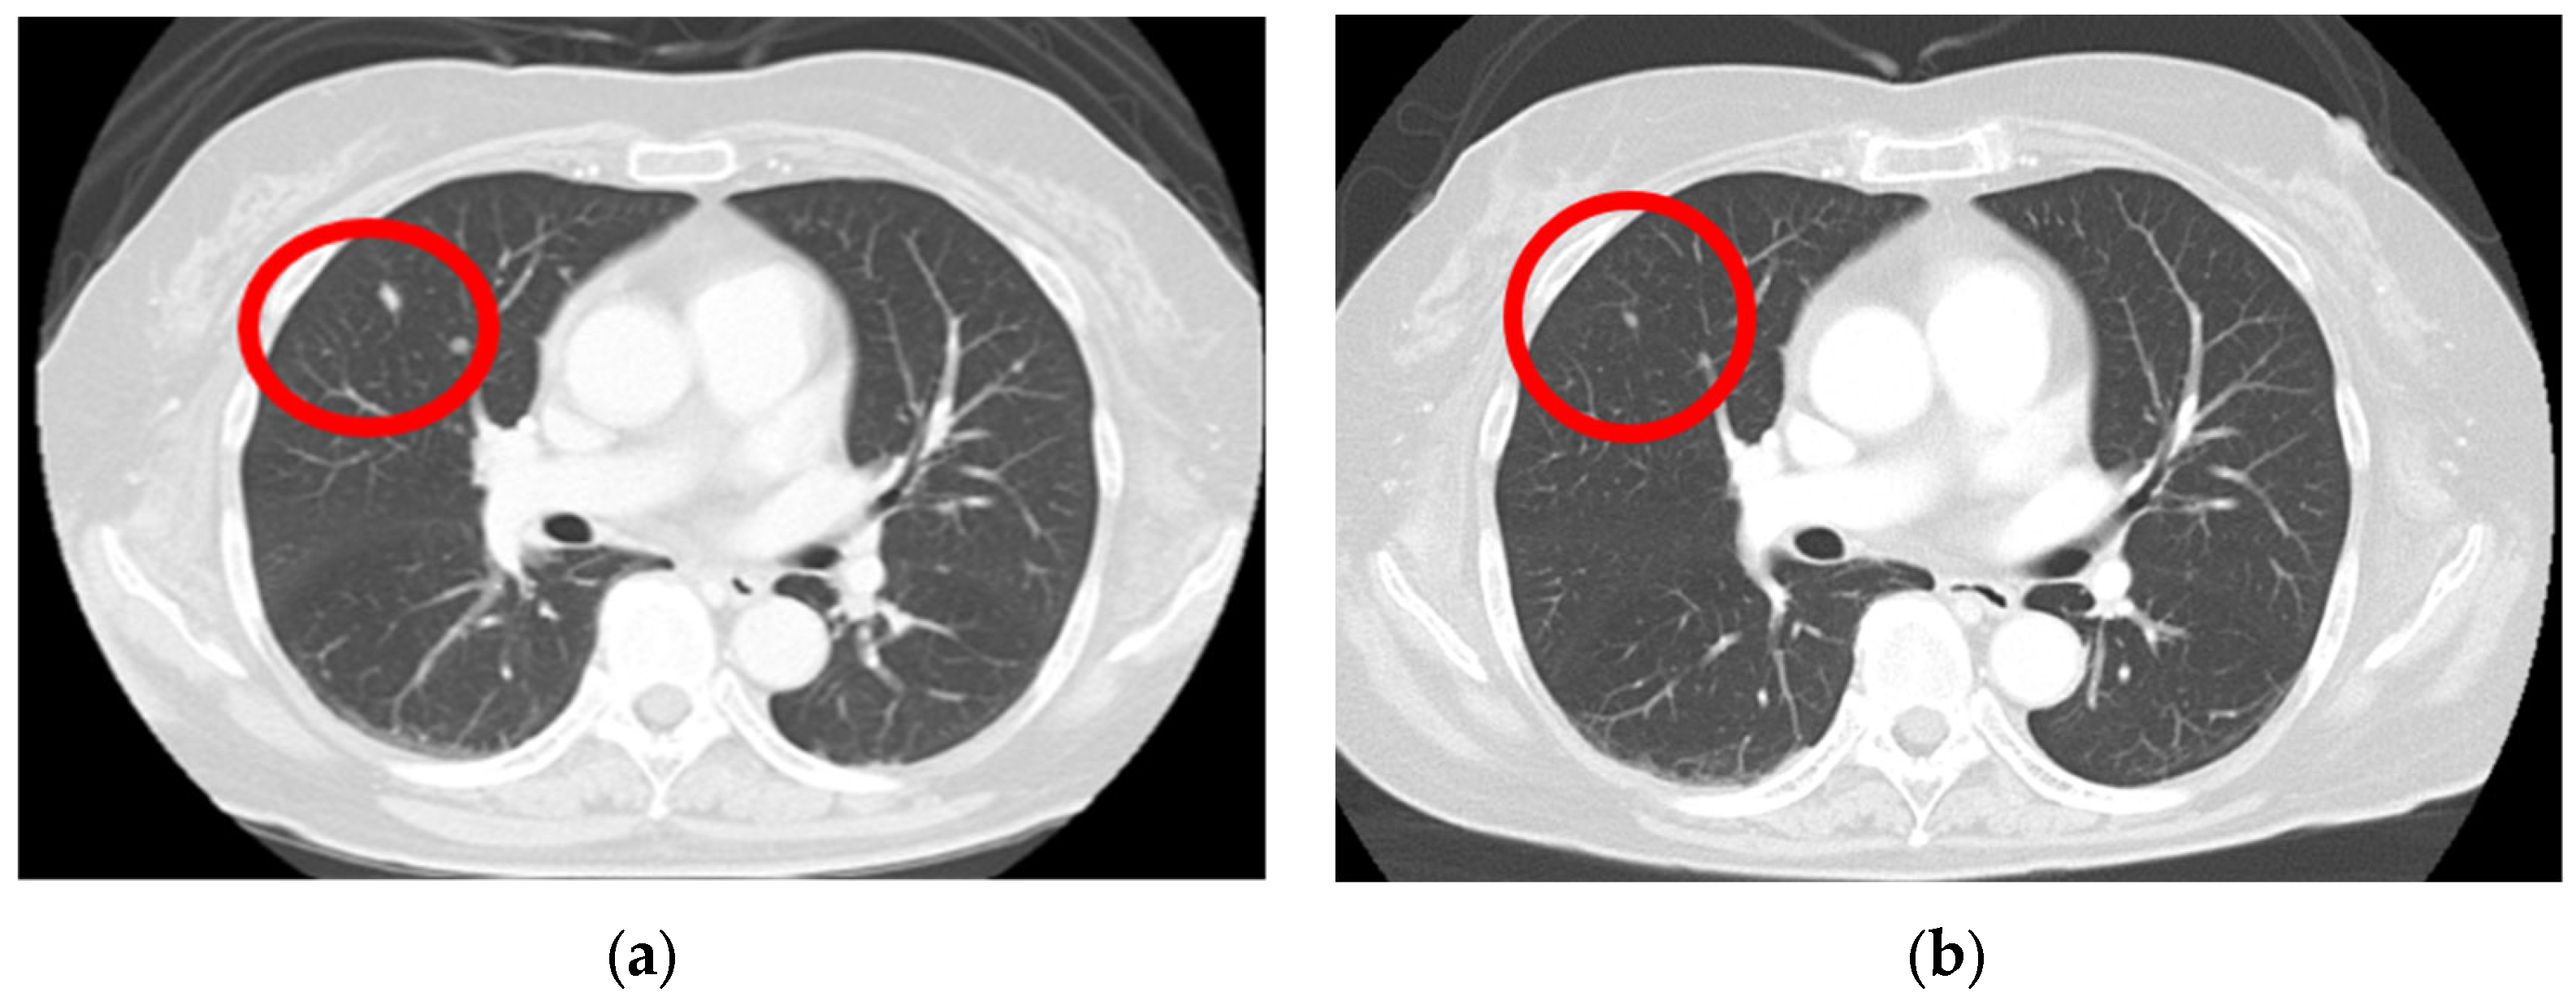

A computed tomography (CT) scan performed from the head to the pelvis to search for metastases revealed a right lung nodule, leading to a diagnosis of lung metastasis (Figure 3a). After endoscopic surgery for gastric mucosal melanoma, pembrolizumab, an ICI, was initiated at 200 mg every 3 weeks. Four months after initiating ICI therapy, the patient developed hypothyroidism, which was considered an irAE, and thyroid hormone medication was administered. Following treatment, her thyroid function normalized, allowing continuation of ICI therapy. For the next 2 years, no new irAEs appeared, and the lung metastatic nodule showed a significant reduction (Figure 3b).

Figure 3.

Lung metastasis is observed before the initiation of immune checkpoint inhibitors (a) (red circle); after the 3-year chemotherapy treatment, the lung metastasis nodule shows a significant regression (b) (red circle).